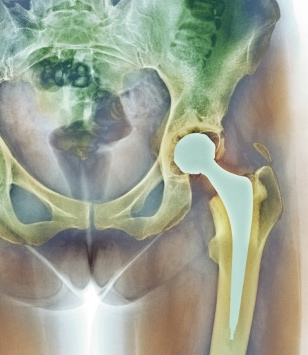

Many patients with the ASR hip have suffered from hip implant failure, which can cause pain, fatigue, walking difficulty, lack of flexibility, hip popping or squeaking, and swelling in the surrounding tissue. Some of these symptoms point to metal poisoning or substantial tissue loss that can never be restored.